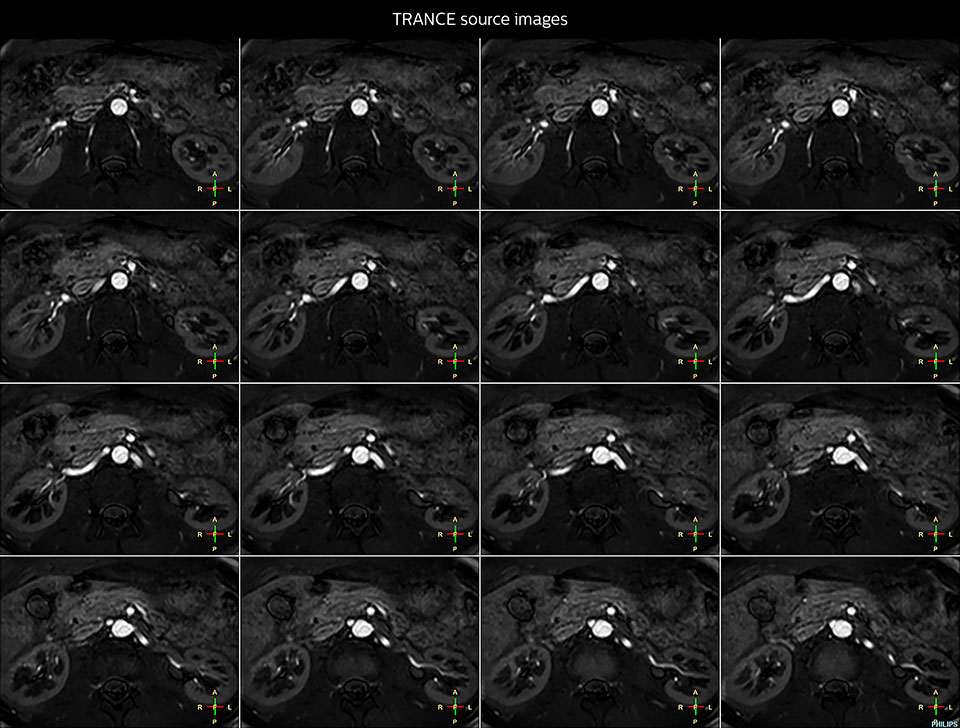

Imaging the renal arteries without contrast agent on Prodiva 1.5T.